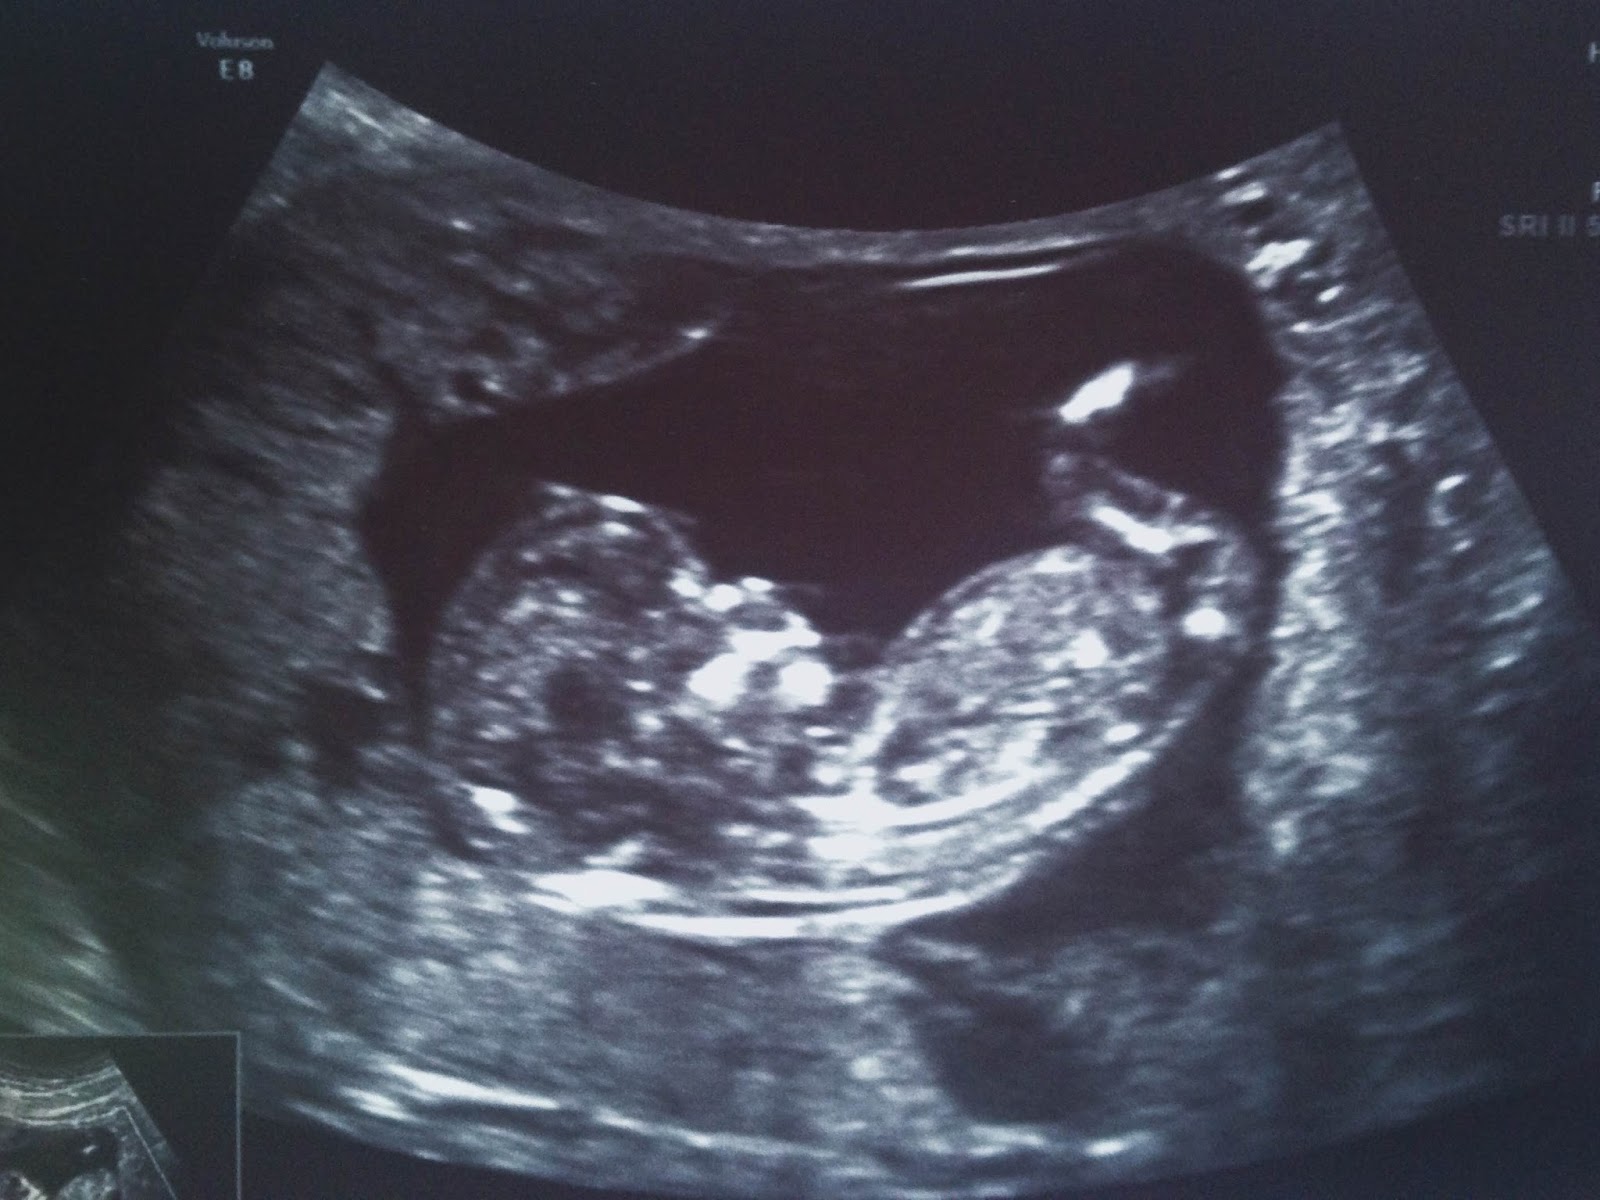

Today I had one of the most amazing experiences of my life. Me and Luke got to go to my first ultrasound and see our little one for the first time. It was pretty surreal as I laid down on the table and pulled my shirt up to expose my belly. I was expecting the gel to be cold like I had seen in movies and TV shows but they actually warm it up so it was really nice. Haha! I wasn't able to see the first part as the tech needed to take some measurements but Luke got to see our baby first and the expression on his face is something I'll always remember. His face looked so proud and amazed all at the same time. The first glimpse I got was of our baby's arm. It was all intact even showing bones and each tiny finger. It was like he or she was waving at us. :) To see the whole body, the face and even a little nose was so remarkable. The heart was beating at 159 beats per minute to be exact. We even got to see our baby swallow which was just amazing and I cannot wait to finally feel it's dancing! This was inside me? Really? It seemed so surreal and I think it has really sunk in for me that I'm truly carrying our baby. It looked nothing short of human that's for sure and so cute.

We even got a 3D Image at our ultrasound. Such a treat!

Hi Mom and Dad! This was my first glimpse at our baby.